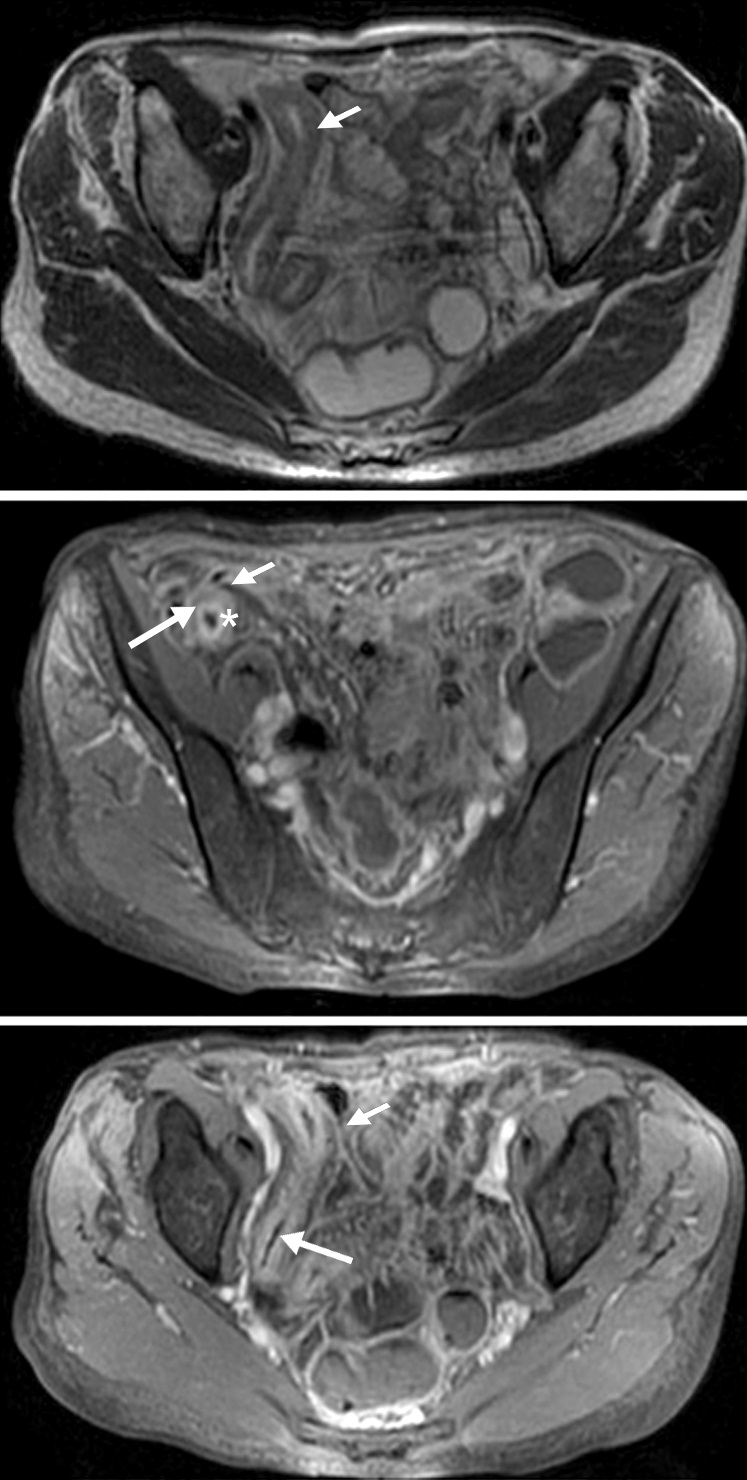

Figura 5

Enfermedad de Crohn

a y b) Secuencias T2 con saturación grasa en el plano axial. Engrosamiento parietal circunferencial de la última asa ileal sin edema que contacta con el colon transverso presentando adherencias con el mismo (flecha). Tracto sinusal que se extiende desde el asa alterada al borde anterior del músculo ilíaco derecho (flecha corta).

c) Secuencia T1 con saturación grasa y gadolinio, pequeña colección líquida en el espesor muscular con realce parietal (punta de flecha)

Figura 6

Paciente de 39 años con enfermedad de Crohn diagnosticada en 2012.

a) Sagital T2, el colon sigmoides presenta disminución de calibre en la unión recto sigmoidea.

b) T2 axial, no hay evidencia de edema submucoso ni otros signos de actividad. En la secuencia cine la estenosis permanecía fija, por lo que se interpretó como secuelar.